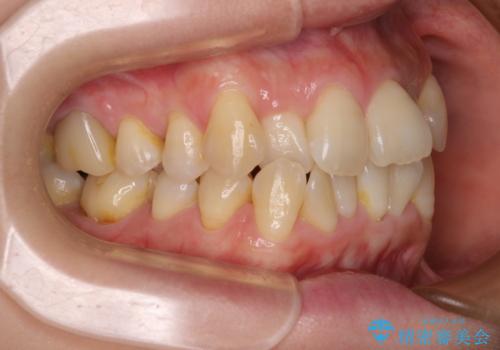

元々の叢生と歯肉退縮傾向になる歯肉であったため、ブラックトライアングルが目立つことが想定されました。

治療過程でブラックトライアングル改善のため、IPR(歯と歯の間を削る)を活用しました。